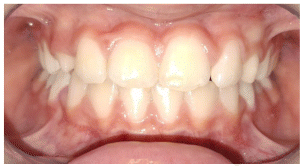

The patient was a growing female child who presented during early mixed dentition with an anterior crossbite associated with a deep overbite and a marked sagittal discrepancy (Figures 12–19). The initial clinical examination revealed a negative overjet, complete anterior deep bite, and a functional Class III occlusal pattern. Extraoral assessment showed a flattened facial profile, while cephalometric analysis confirmed a skeletal imbalance characterized by increased SNA and SNB values, an ANB of 0°, negative Withs appraisal, and significant dentoalveolar compensations, including proclination of both upper and lower incisors (Table 3). The vertical pattern was predominantly hypodivergent, suggesting a high risk of unfavorable mandibular growth progression if left untreated. Given the patient’s young age and growth potential, an early interceptive treatment was planned to use the AMCOP® TC appliance, with the aim of correcting the anterior crossbite, improving neuromuscular balance, and guiding sagittal and vertical development during growth. The appliance was worn nightly and for additional daytime hours, according to patient compliance.

After 18 months of treatment, a clear clinical improvement was observed. Intraoral examination demonstrated complete correction of the anterior crossbite, with establishment of a positive overjet and normalization of the anterior occlusal relationship. The deep bite was reduced, allowing more functional anterior guidance. Occlusal relationships improved toward a stable dental Class I, and the need for excessive dentoalveolar compensation was reduced. Cephalometric reassessment showed an overall improvement in sagittal relationships and incisor inclinations, with a trend toward normalization of the previously altered parameters. These findings indicate that early functional therapy with the AMCOP® TC appliance was effective in intercepting the developing Class III malocclusion, improving occlusal function, and potentially reducing the severity of future skeletal discrepancies (Table 4).